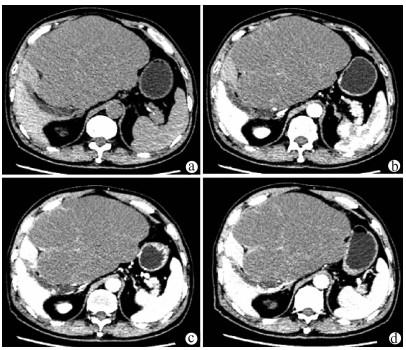

A preliminary study on percutaneous transhepatic drainage combined with sequential percutaneous nephroscopy in treatment of refractory liver abscess

Changhu DUAN, Xiaochen LIU, Jianlong DING, Jianfeng DUAN, Xirong ZHAO, Fan YANG, Ling WU, Lifei ZHAO, Sheng TAI

2021, 37(11): 2622-2625. DOI: 10.3969/j.issn.1001-5256.2021.11.026

Abstract(1123) HTML (227) PDF (2925KB)(75)

Abstract:

Objective  To investigate the clinical effect of percutaneous transhepatic drainage combined with sequential percutaneous nephroscopy for necrosectomy and drainage in the treatment of refractory liver abscess after transcatheter arterial embolization (TACE).  Methods  A retrospective analysis was performed for three patients with refractory liver abscess after TACE in The Affiliated 3201 Hospital of Xi'an Jiaotong University School of Medicine from January 2018 to December 2020, and among the three patients, one had the formation of liver abscess after TACE for hepatic metastases after pancreaticoduodenectomy, one had liver abscess after repeated TACE for massive hepatocellular carcinoma, and one had secondary liver abscess after TACE for traumatic hepatic rupture. All three patients received percutaneous transhepatic drainage and sequential percutaneous nephroscopy for the treatment of refractory liver abscess, and their specific treatment process was summarized.  Results  All three patients were diagnosed with refractory liver abscess based on CT, routine blood test, procalcitonin, blood culture, and clinical manifestation. Percutaneous transhepatic catheterization under the guidance of conventional ultrasonography or CT and effective antibiotics had an unsatisfactory therapeutic effect, and after sequential percutaneous nephroscopy was performed for necrosectomy and drainage, liver abscess was cured and the patients had good prognosis.  Conclusion  For refractory liver abscess after TACE, when routine puncture treatment has an unsatisfactory therapeutic effect or a patient cannot tolerate surgical operation, percutaneous transhepatic drainage combined with sequential percutaneous nephroscopy is safe and effective in the treatment of refractory liver abscess.